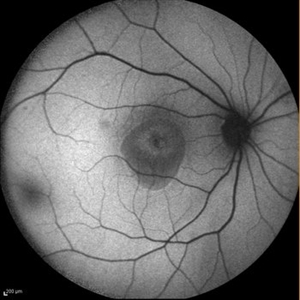

Central Areolar Choroidal Dystrophy Central Areolar Choroidal DystrophyJul 7 2015 by Hamid Ahmadieh, MD Fundus autofluorescence of both eyes of a 58-year-old man with progressive loss of vision. VA OD is 20/60 and VA OS is 20/400. Photographer: Soulmaz Shahmohammad, Negah Eye Center, Tehran, Iran Imaging device: Specteralis Condition/keywords: central areolar choroidal dystrophy (CACD), fundus autofluorescence (FAF)

Central Areolar Choroidal Dystrophy Central Areolar Choroidal DystrophyJul 7 2015 by Hamid Ahmadieh, MD Color fundus photograph of both eyes of a 58-year-old man with progressive loss of vision. VA OD is 20/60 and VA OS is 20/400. Photographer: Soulmaz Shahmohammad, Negah Eye Center, Tehran, Iran Imaging device: Topcon Condition/keywords: central areolar choroidal dystrophy (CACD), color fundus photograph